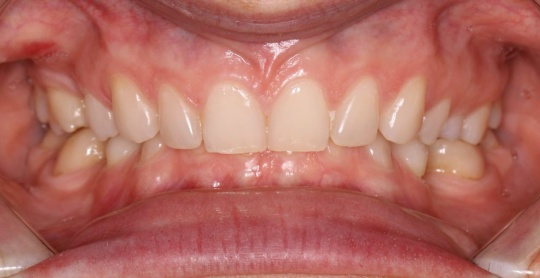

ДО

Была поставлена задача расслабить очень сильные жевательные мышцы и вывести сустав из компрессии, поэтому был сплинт в цс, потом прямые накладки и брекеты для освобождения пространства под имплантацию в зоне отсутствующих Зубов